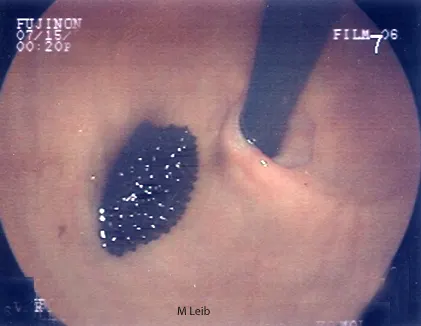

Large gastric ulcer in a 10-year-old Rottweiler. Black clotted blood is adhered to the crater of the large ulcer. The horizontal ridge is the angularis incisura; the antrum is located below the angularis.